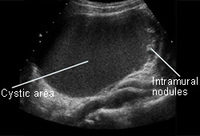

Ovarian cyst with nodules on ultrasound

From the collection of Justin C. Chura, MD, Cancer Treatment Centers of America, Philadelphia, PA